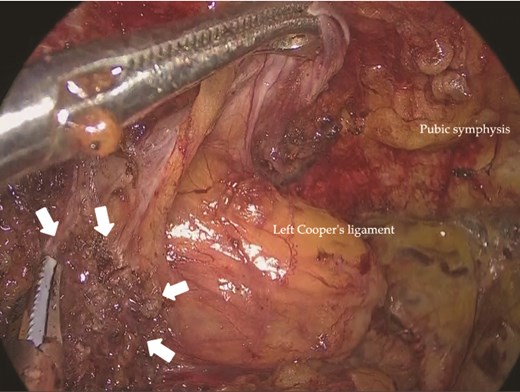

Under general anesthesia, a 12-mm camera port was inserted through the umbilicus, and two 5-mm ports were placed in the lower quadrants. Laparoscopic exploration revealed two mesh plugs on the left with fibrotic scarring and adhesions, which obscured the exact hernia orifice (Fig. 2). An incidental right direct hernia (M3) was also identified intraoperatively. Because severe adhesions were anticipated on the left, the operation was initiated on the right. A high peritoneal incision was initiated medial to the right anterior superior iliac spine (Fig. 3). The pseudosac was dissected while preserving the retropubic fascia, and the preperitoneal dissection was extended across the midline into the left side (Fig. 4). Approaching from the contralateral side allowed progressive entry into the adhesion-laden region through an unscarred plane, improving visualization and minimizing peritoneal injury.

Laparoscopic view of the left inguinal region showing two previously placed mesh plugs (arrows). No definite recurrent hernia orifice was identified. Dense adhesions were present around the plugs.